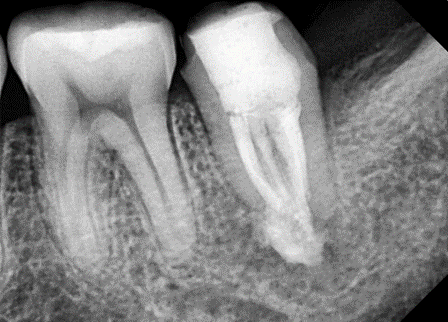

제가 근래에 만난 C형근관을 소개합니다.

![[신경치료] 아래 어금니를 신경치료 할 때 치료할 때 알아야 할 것 (C형근관,고난이도치료) 관련 이미지 9](https://pub-9f2bb3498faf4d1d8714b41df24753e3.r2.dev/content/clinics/archive/nqmm0udu86/naver_blog/honeybeevuvu/assets/by_hash/fd9894626b80ca017415b65191ddb6fdf8dc092b65cd5990929c538cd1085212.png)

본원의 C형 근관 치료 예시 -30대 여성